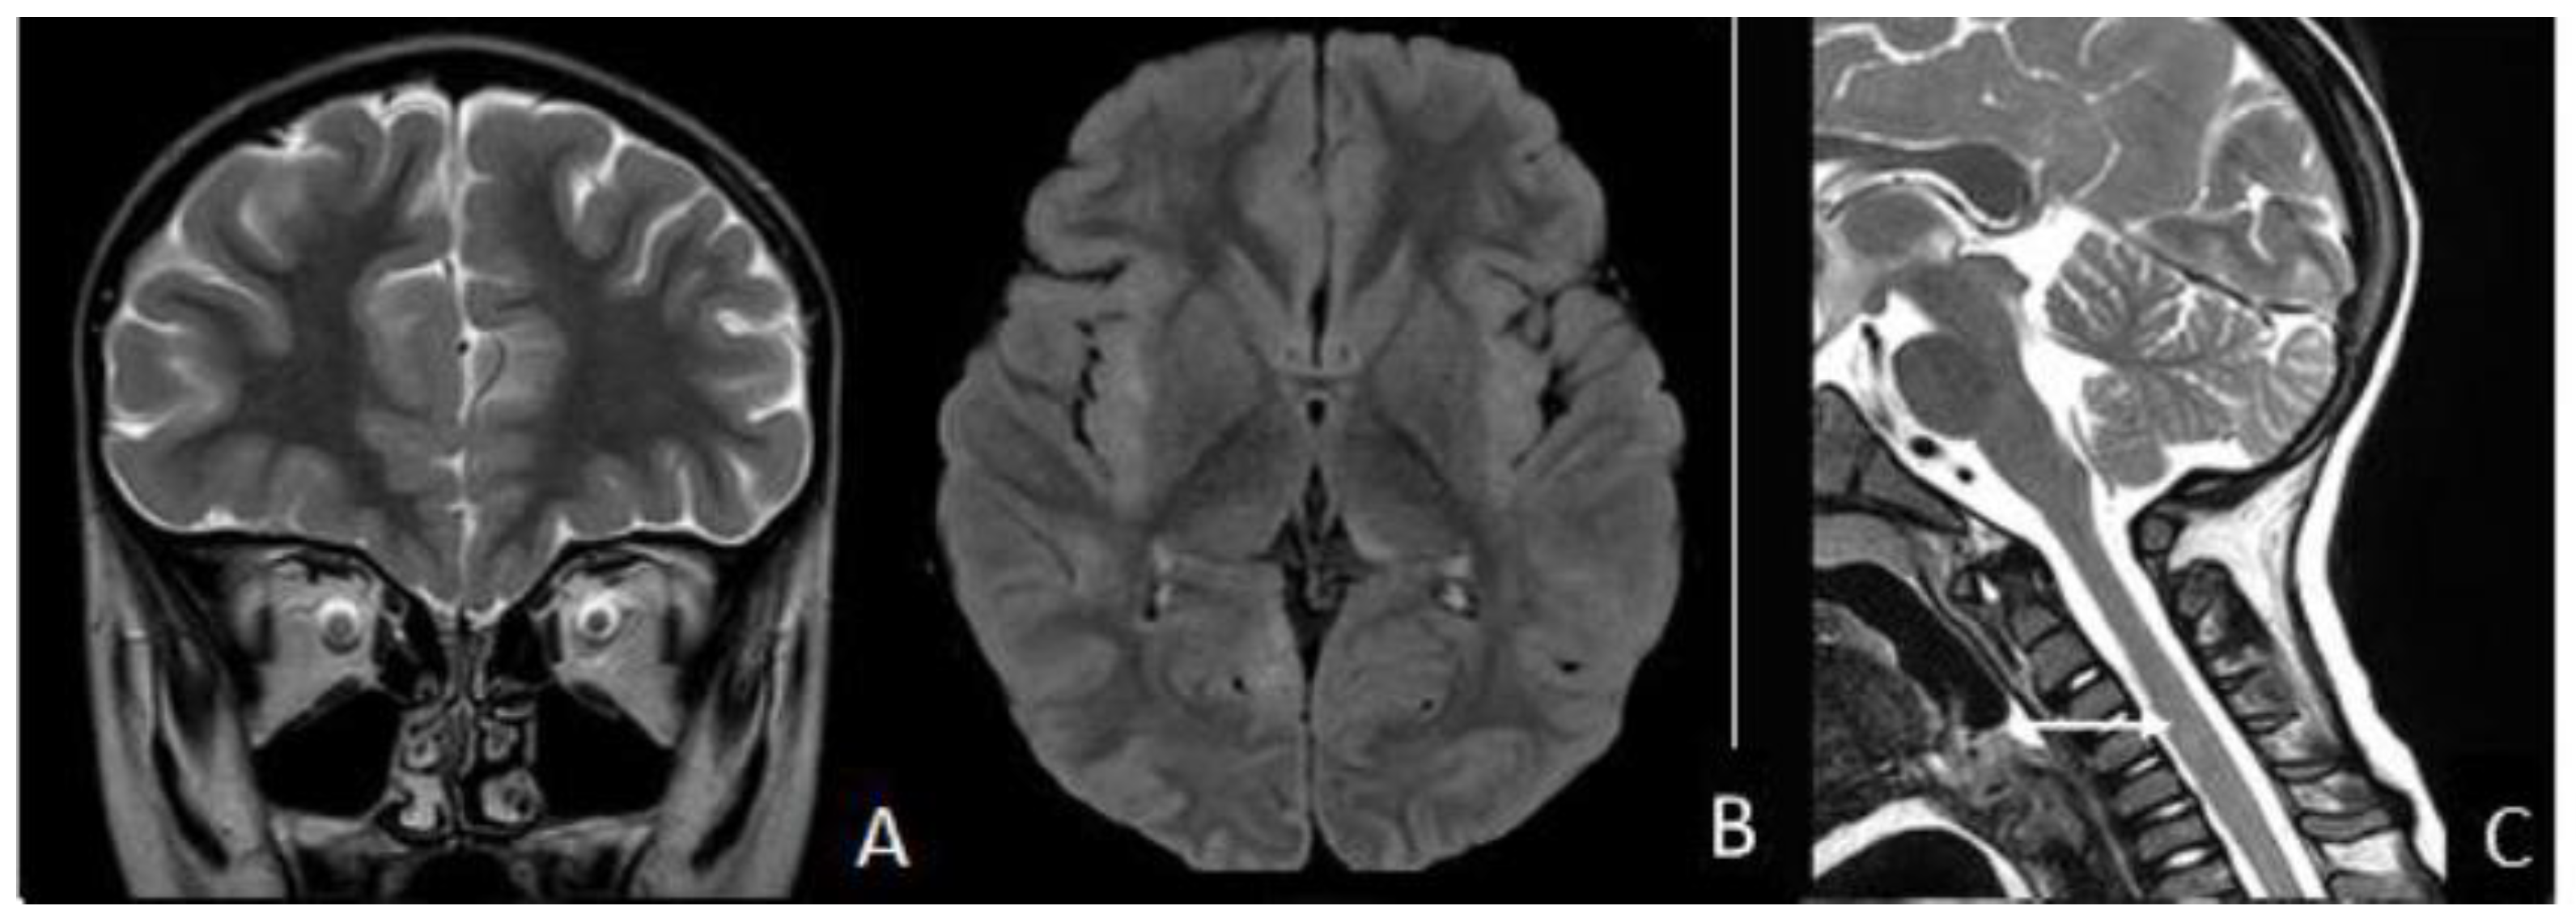

2. Case Presentation